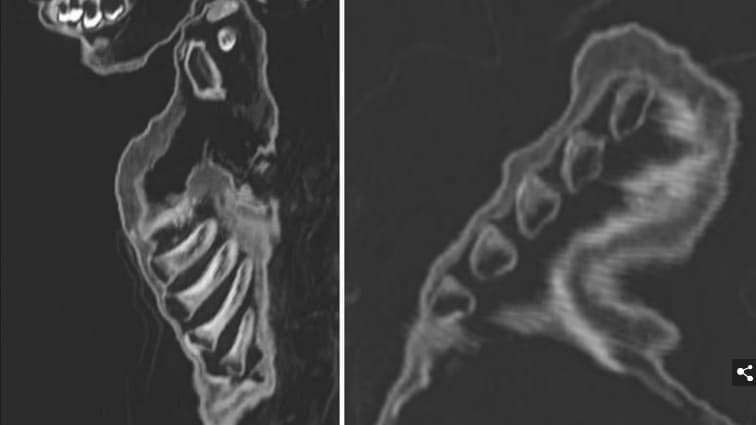

그의 몸은 폐렴과 비타민 D 결핍의 징후를 보여주는 CT 검사를 받았고, 방사성 탄소 연대 측정법은 그가 언제 죽었는지에 대한 다양한 날짜를 제공하기 위해 조직과 피부에 시행되었다.

오늘 Frontiers in Medicine에 발표된 이 연구를 위해, Nerlich 박사의 팀은 그의 치아를 연구했고 그의 뼈 길이를 측정했는데, 이것은 아이가 죽었을 때 12개월에서 18개월 사이였다는 것을 암시했다.